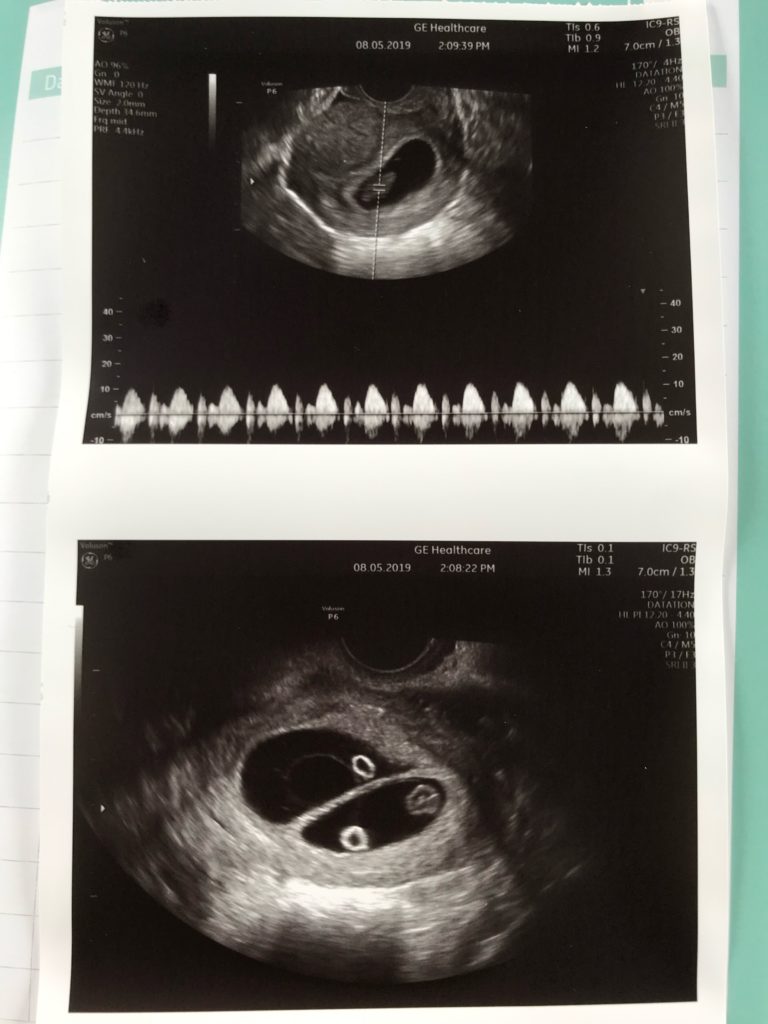

Les semaines avant le première échographie étaient remplis de questions,mais tellement de bonheur en même temps.. Le jour de l’échographie est arrivé,nous ne nous doutions vraiment de rien jusqu’à ce qu’on voit sur l’écran deux petites poches et l’annonce de ma gynécologue qui m’a directement confirmer ma grossesse gémellaire (de jumeaux). Je me suis effondrée,sans doute la peur qui m’a envahie.. J’ai entendu leurs petits cœurs, c’est à ce moment là que j’ai réalisé que ce n’étais pas un rêve mais bel et bien deux petits bébés qui étaient dans mon ventre, on n'avait pas vraiment imaginé ce premier rendez vous comme ça. Mais l’émotion s’est très vite transformé en pleins d’amour et en une immense joie!